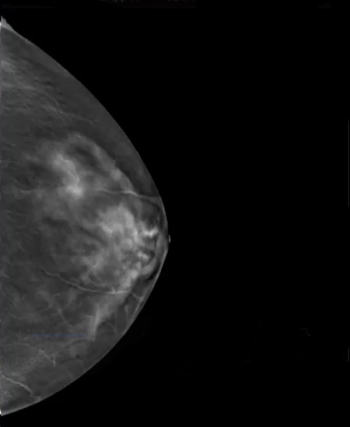

New research suggests that AI-powered assessment of digital breast tomosynthesis (DBT) for short-term breast cancer risk may help address racial disparities with detection and shortcomings of traditional mammography in women with dense breasts.

Emerging research from the RSNA conference suggests that two-dimensional mammography would only detect 41 percent of detectable breast cancer.

In a recent interview, Sarah Friedewald, MD, discussed new study findings for an adjunctive AI software for digital breast tomosynthesis (DBT) that revealed nearly equivalent sensitivity and specificity rates for breast cancer across a diverse cohort.

Originally cleared by the FDA in 2021, the SmartMammo Dx software for digital breast tomosynthesis (DBT) can now be utilized with the Senographe Pristina mammography systems from GE HealthCare.